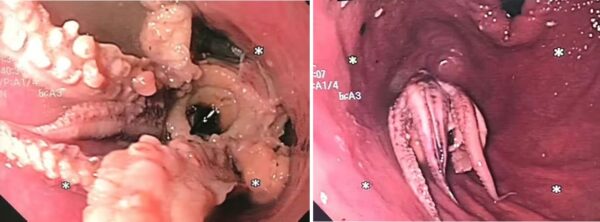

Lelaki ini alami kesukaran menelan makanan rupanya tersekat sotong kurita dalam kerongkong!